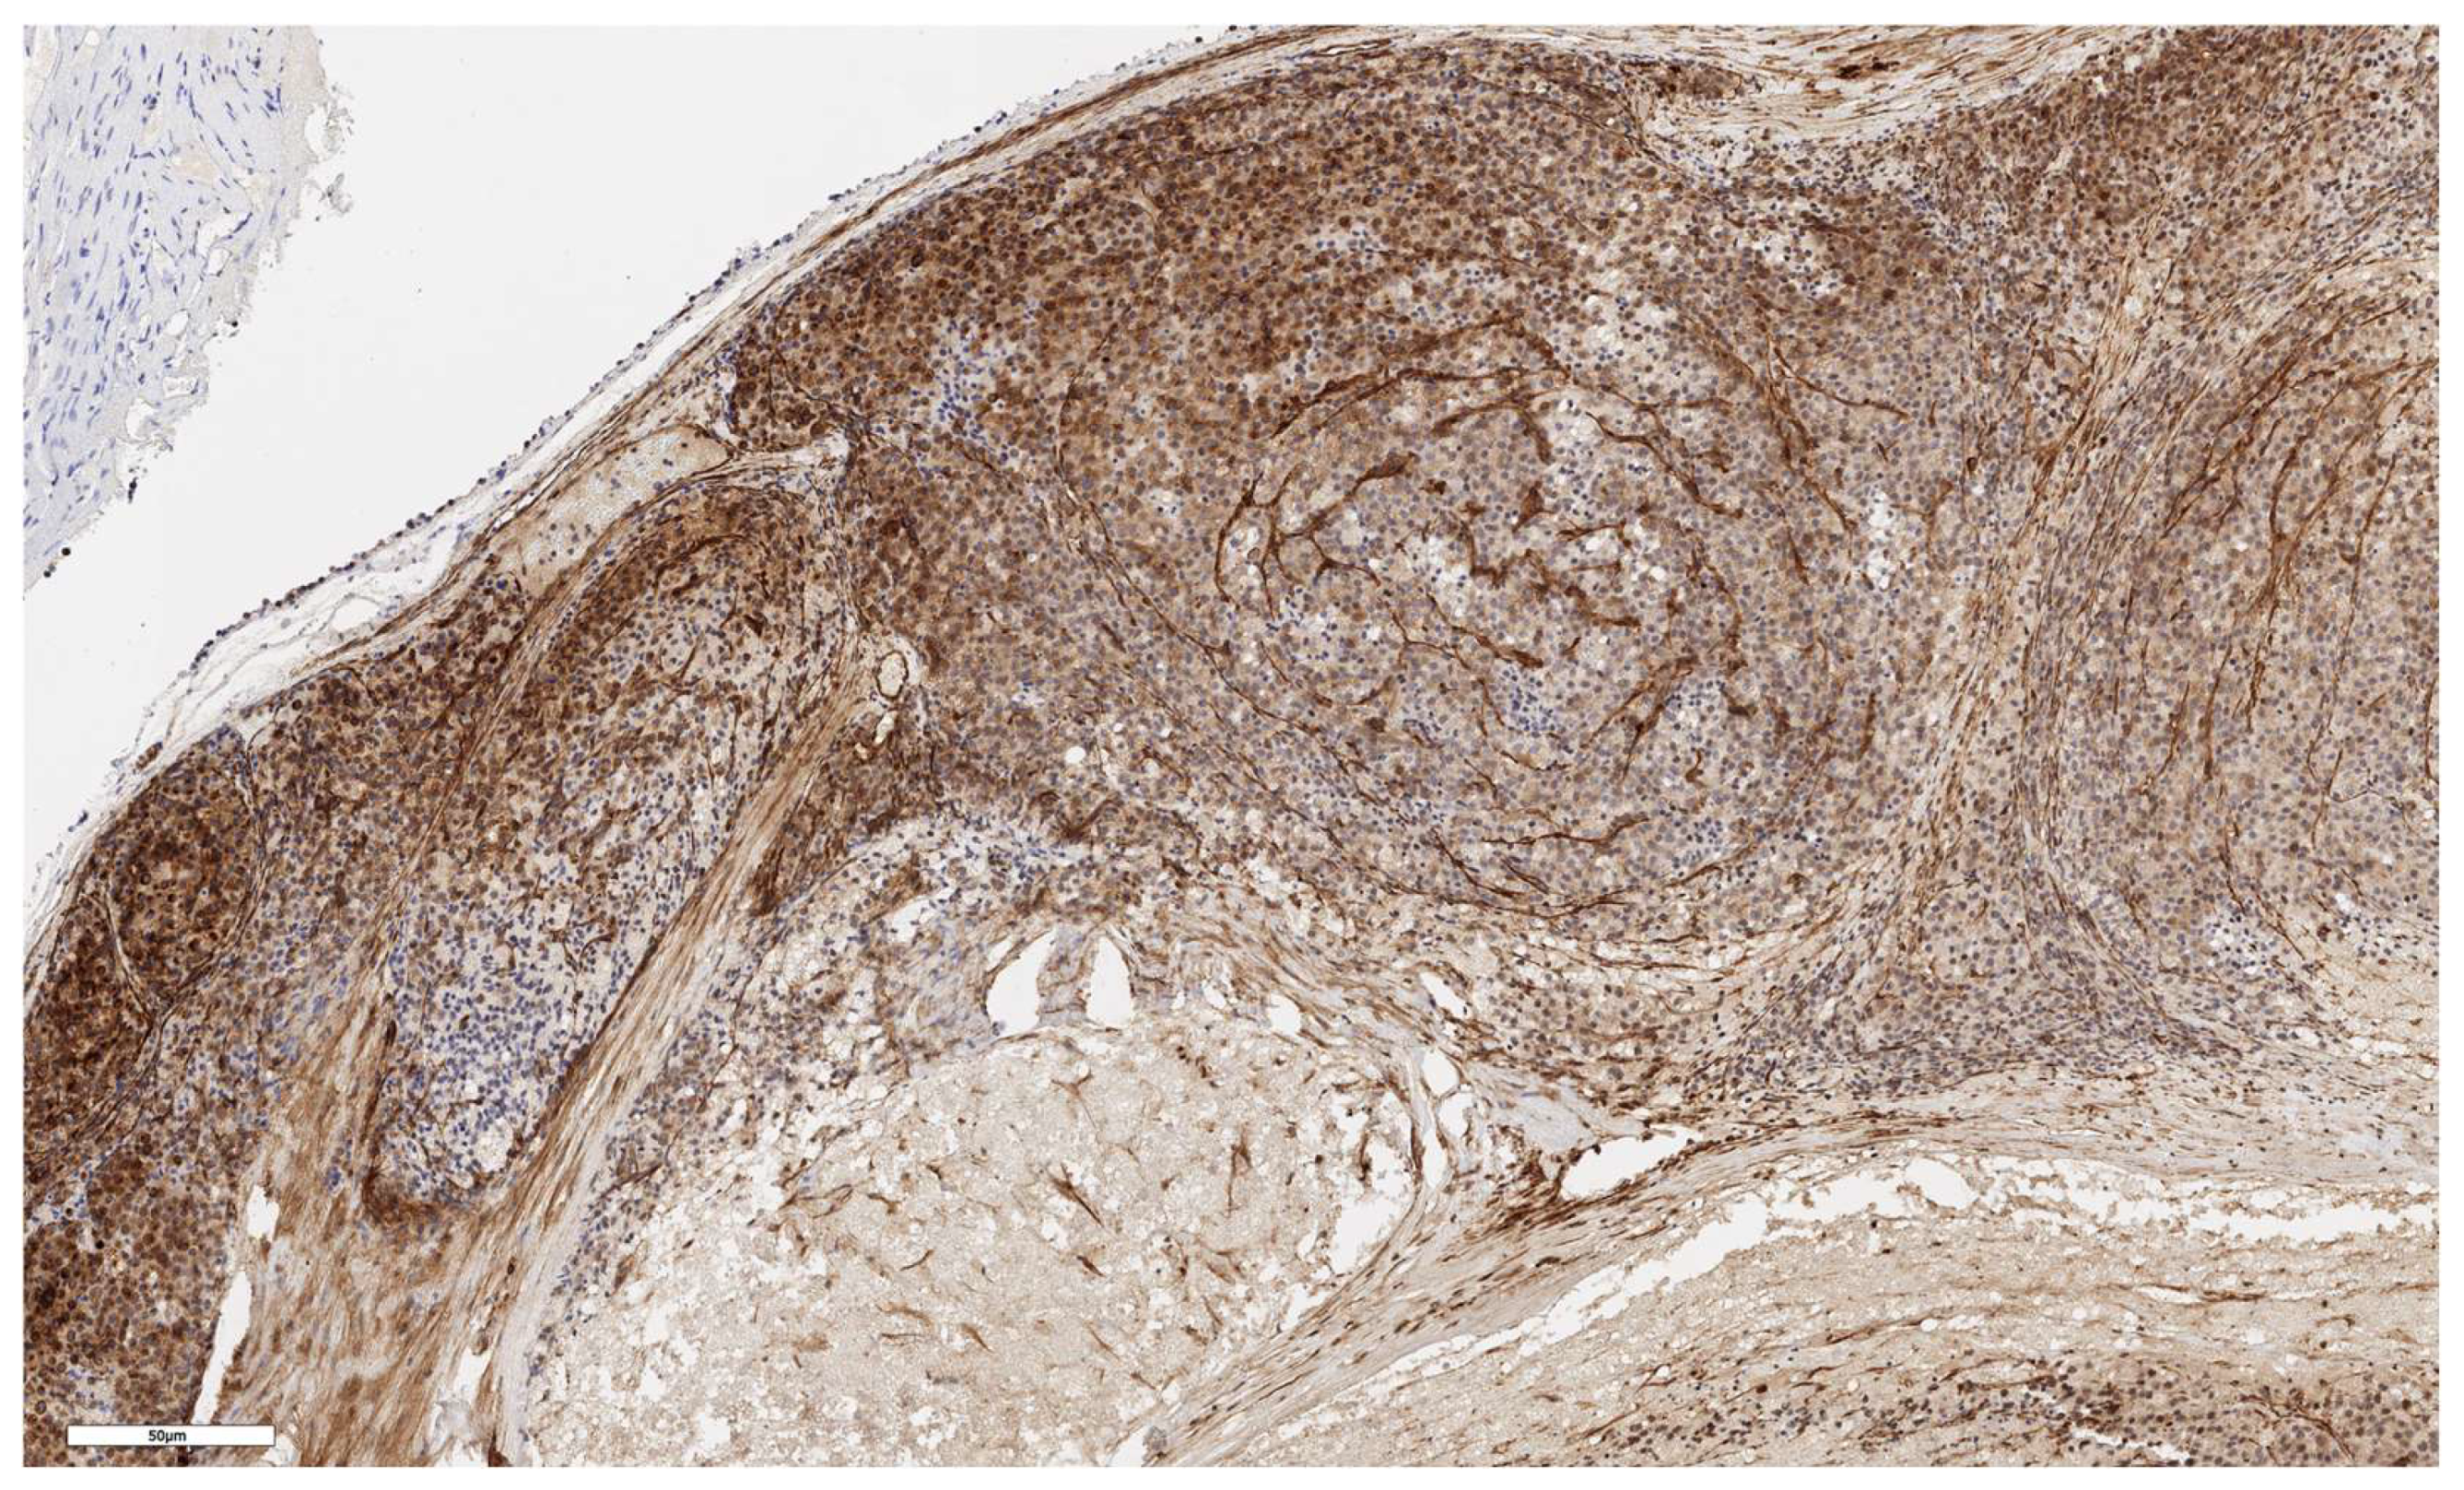

An analysis of the association between CD90 expression and the clinicopathological data of patients was conducted (Table 2). The number of CD90+ cells in the tumor parenchyma was relatively higher in samples of conventional and mixed histological subtypes compared to other histological subtypes of ACC (Figure 2, Figure 3, Figure 4 and Figure 5); however, these differences did not reach statistical significance (p = 0.161). No significant differences in CD90 expression beneath the tumor capsule were found across histological subtypes either.

Figure 3. Conventional subtype of ACC. CD90 positive cells under the tumor capsule, x60.